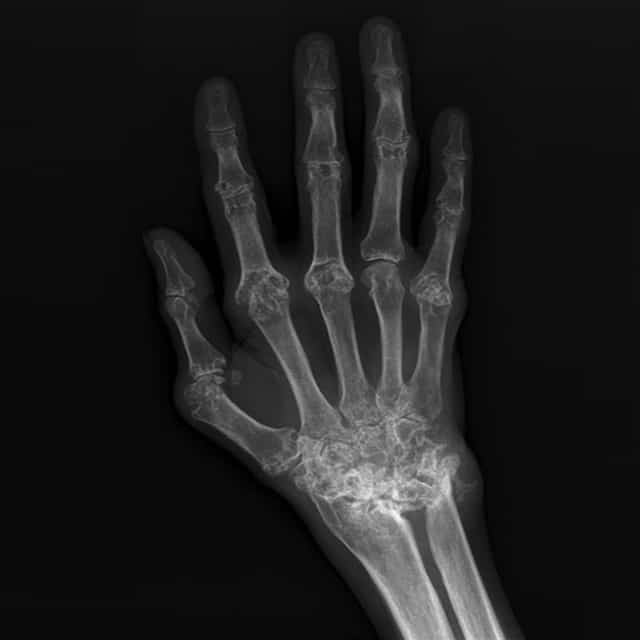

Rheumatology is a branch of medicine that is dedicated to the study of inflammation ie. swelling, warmth, pain, redness; of the structures that that make up the framework of the body, ie. joints, bones, muscles, connective tissue. The most common condition addressed is arthritis which refers to inflammation of the joints. Arthritis can be caused by a multitude of different conditions. Rheumatology also deals with complex, rare, serious, systemic autoimmune diseases that can affect many organ systems all at the same time. Lomibao Rheumatology and Wellness Care provides specialized care for patients with many different types of rheumatologic conditions, many of which are listed below.